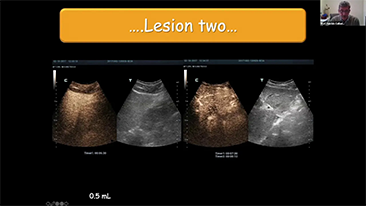

Para las lesiones hepĂĄticas focales, como el hemangioma o el cĂĄncer de hĂgado, el diagnĂłstico por imĂĄgenes mediante ecografĂa con contraste cumple un papel importante. La tecnologĂa de diagnĂłstico por imĂĄgenes con contraste UWN+ (no lineal ultraancha) puede ayudar a obtener una mejor penetraciĂłn, una mayor relaciĂłn contraste-tejido, con un IM mĂĄs bajo y una observaciĂłn del tiempo de perfusiĂłn mĂĄs prolongada.